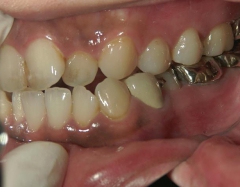

矯正歯科 治療前矯正歯科 治療前

矯正歯科 治療前 上顎を装置(QH)で拡大後ワイヤー矯正へ移行、右下5番左下4番 計2本抜歯叢生改善

no.28_6958_治療前_右.jpgno.28_6958_治療前_正面.jpgno.28_6958_治療前_左.jpg